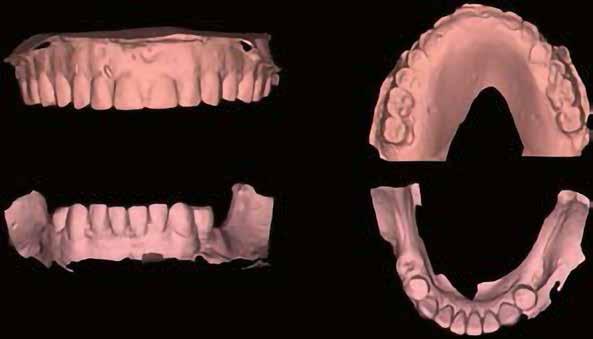

A-PRF membránokkal borítottuk (7. ábra). A mukogingivális lebenyt – annak megnyújtása nélkül – a helyére fektettük és varratokkal rögzítettük, per primam sebzárást nem végeztünk (8., 9. ábra). A varratokat 2 hét után távolítottuk el, a varratszedésig a sebgyógyulás támogatására per os 1000 mg/nap C- és 12 000 NE/nap D-vitamint adtunk (20). A műtéti beavatkozást 24 hét gyógyulási időszak követte, melynek során sem helyi, sem gyógyszeres kezelés nem történt, az esztétikum javítása érdekében a páciens ideiglenes kivehető fogpótlást használt. A csontos gyógyulás ellenőrzése és az implantáció tervezése céljából állcsonti CT felvételt készítettünk, illetve lenyomatvételt végeztünk. A CT felvételen tökéletes csontos gyógyulást észleltünk, az alveolaris csont volumene teljes mértékben megtartott volt (10. ábra), a klinikai kép is ennek megfelelően alakult (11., 12. ábra)

A Trishape Implant Studio™ a korábbi csont augmentáció területén, a felső állcsontnál áltagosnak számító D2-D3 csontminőséget jelzett (13. ábra). A lenyomat alapján készített gipszmodellt szkennelve virtuális mintát nyertünk. A CBCT felvétel és a virtuális modell adatait a Dual Scan protokoll (21) elveinek megfelelően használtuk fel az implantációs sablon (New Age Dental Kft, Nemeskéry Károly) készítéséhez (14., 15., 16. ábra). Az implantátum (Ankylos C/X A11) behelyezése teljesen navigált módon, 35 Ncm primer stabilitással történt (17., 18. ábra). Az implantátumra a fogtechnikus (D1 Dental Kft., Garamvári Csaba) által előzetesen

elkészített csavarozott, ideiglenes fogpótlást rögzítettünk a gyártó által előírt 15 Ncm-es nyomatékkal, az ideiglenes korona az okklúzióban és artikulációban nem vett részt (19., 20., 21. ábra). A front- és prémoláris régióban, amennyiben lehetséges, mindig nyílt gyógyulási protokollt választunk, azonnali ideiglenes restaurátumot készítve, így biztosítva elegendő időt a lágyrészek maturációjához (23, 24, 25, 26, 27). A kontrollvizsgálatok során havonta ellenőriztük az ideiglenes fogpótlás és az implantátum stabilitását, valamint a lágyrészek állapotát, korrekciós beavatkozás vagy az ideiglenes korona emergencia-profiljának változtatása nem volt szükséges (22. ábra). Két hónapos terhelésmentes időszakot követően, csont-tréninget alkalmaztunk részleges terheléssel, a teljes terhelést a hatodik hónap végére értük el, és megkezdtük a definitív protetikai ellátást. Az ideiglenes restaurátum eltávolításakor az alveoláris struktúrák tökéletes gyógyulását észleltük, a páciens ínye békés, reakciómentes volt, megfelelő mennyiségű keratinizált, feszes ínnyel rendelkezett (23. ábra). Az implantátum stabilitása Periotest-tel -8 értékű volt. Cerec Omnicam rendszerrel digitális lenyomatot vettünk (24. ábra), és a fogtechnikus (Prodont Silver Kft., Panyi János) által ragasztott, csavarozott hibridkerámia koronát készíttettünk nem indexált Ankylos C/ titanium-base fej felhasználásával, amelyet az előírás szerinti 15 Ncm-es nyomatékkal rögzítettünk (25., 26 ábra), majd ellenőriztük az okklúziót és az artikulációt (27. ábra). A beavatkozást követően 6 hónappal az alveoláris struktúrák stabilak, a röntgenfelvételen a csontállomány megtartott, a beteg panaszmentes, rágó funkciója kifogás-